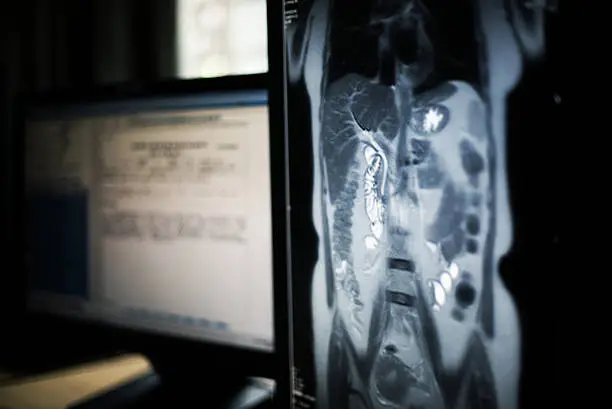

간경화는 간이 점차적으로 딱딱해지고 손상되는 만성 질환으로, 간의 기능이 저하되어 여러 가지 심각한 합병증을 초래할 수 있습니다. 간경화의 초기 단계에서는 증상이 미미할 수 있지만, 이를 치료하지 않고 방치하게 되면 점차적으로 여러 합병증이 발생할 수 있습니다. 이러한 합병증들은 삶의 질을 급격히 떨어뜨리고 심한 경우 생명에 위협이 될 수 있기 때문에 주의가 필요합니다.